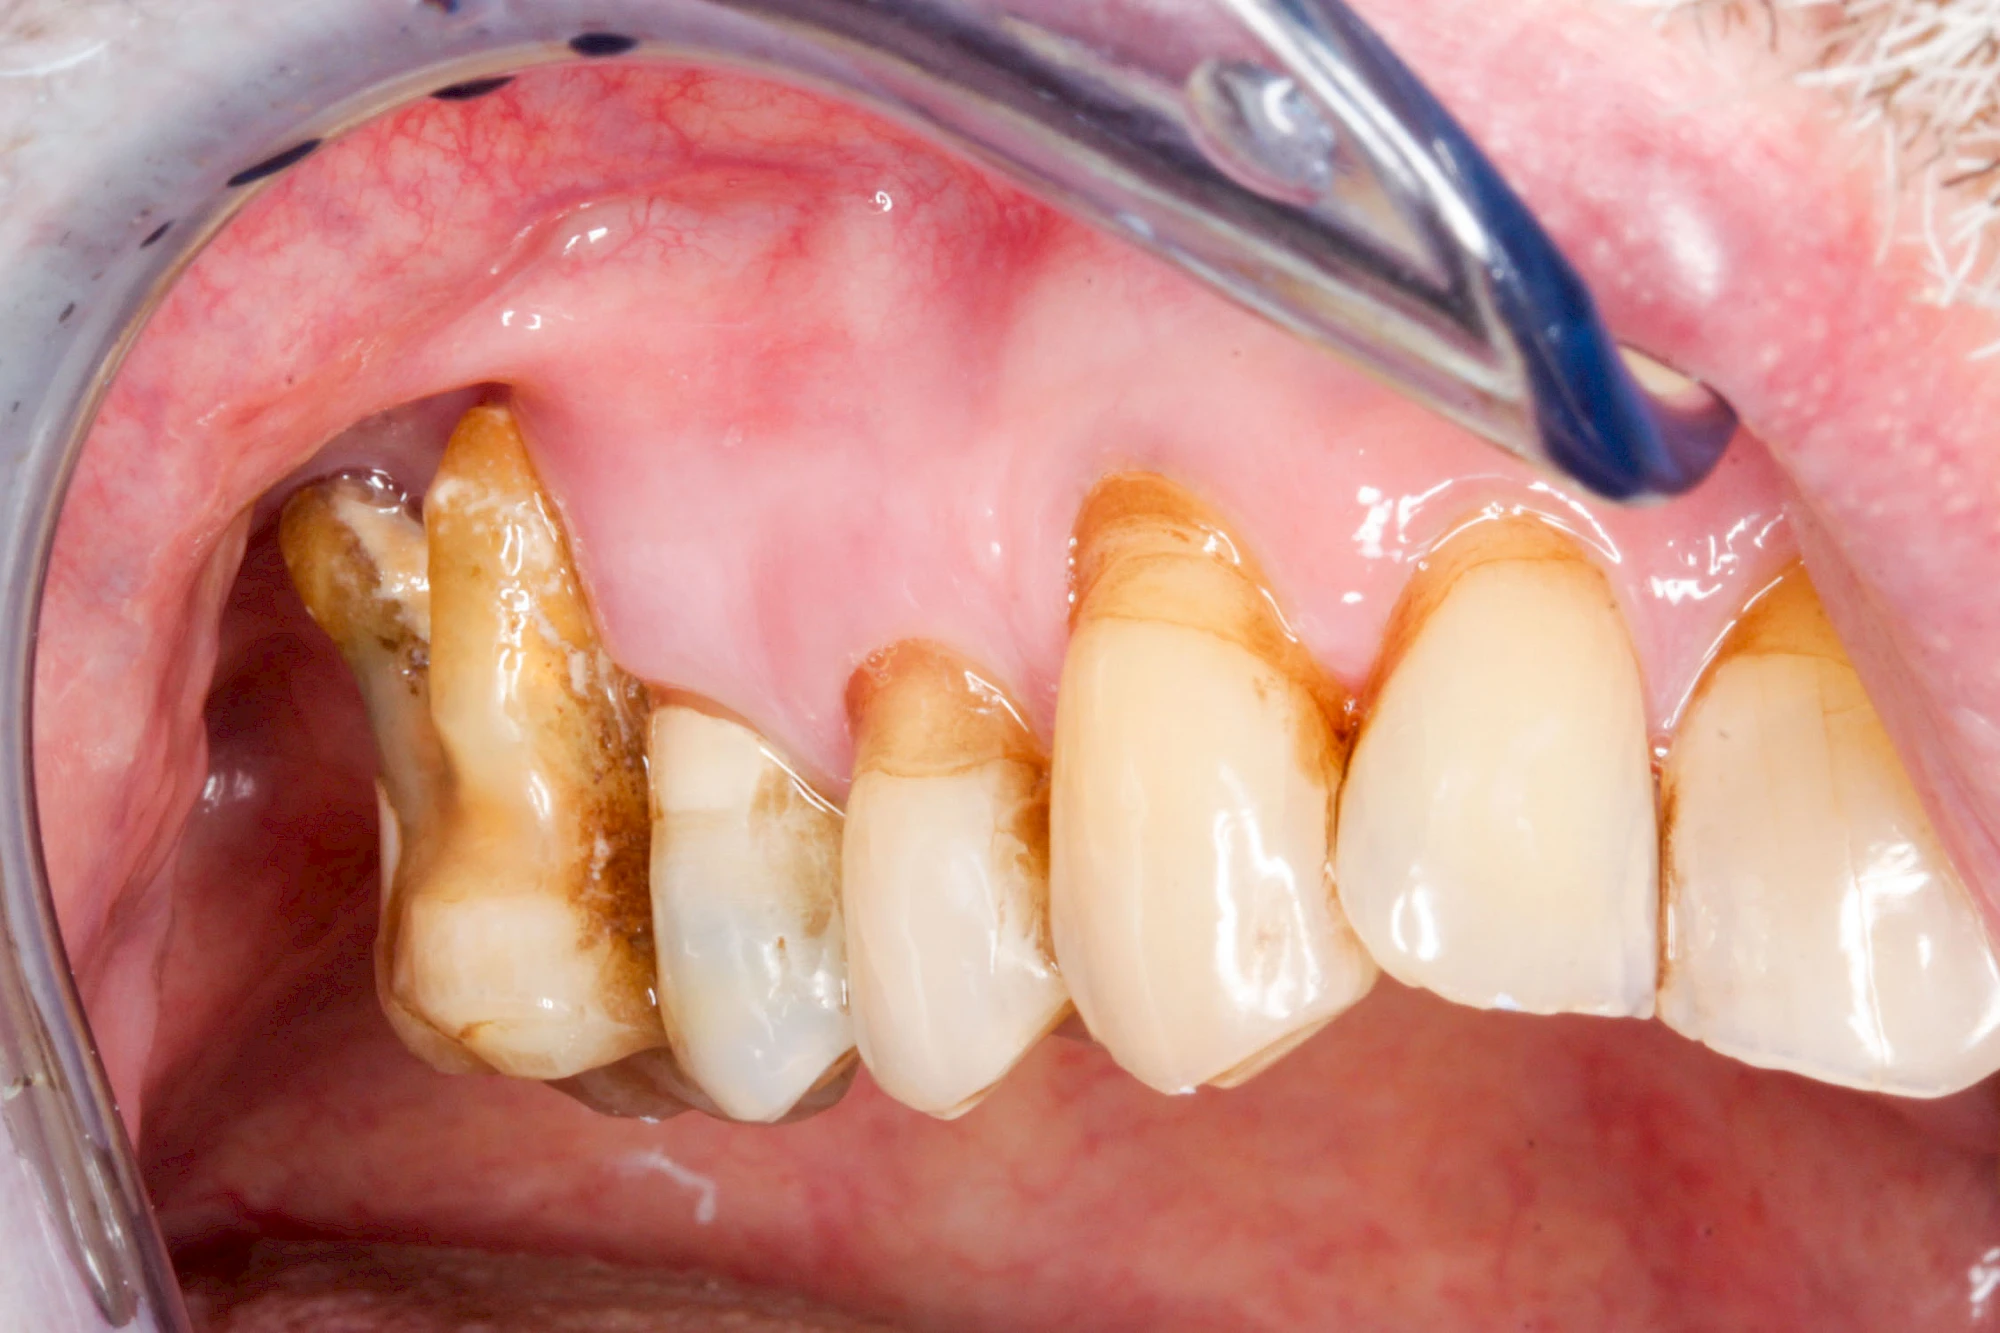

Ist zunächst nur das Zahnfleisch von der Entzündung betroffen, spricht man von Gingivitis. Später, wenn auch der Knochen um die Zähne herum entzündet ist, spricht man von einer Parodontitis. Bei der Parodontitis wird der Knochen nach und nach abgebaut und das Zahnfleisch zieht sich zurück. Die Zahnhälse und Zahnwurzeloberflächen liegen mehr und mehr frei. Die Zähne werden zunehmend lockerer und fallen schließlich aus.

Sonderform: Fistel

Bei einer Fistel hat sich meist eine Entzündung (manchmal auch Erreger selbst) z. B. aufgrund von Karies oder aufgrund eines Unfalls über den Zahnnerv und die Wurzelspitze (Apex) in den umliegenden Knochen ausgebreitet (apikale Parodontitis) und schnell einen Weg durch den umgebenden Knochen und die aufliegende Schleimhaut in die Mundhöhle gebahnt.

Fisteln sind in der Regel nicht schmerzhaft und fallen häufig als kleine Öffnung weiter entfernt vom Zahnfleisch nahe der Umschlagfalte auf. Aus der Fistelöffnung entleert sich spontan gelbliches Sekret (Eiter) oder es lässt sich mit dem Finger ausstreichen. Manchmal beschreiben die betroffenen Menschen immer wieder einen komischen Geschmack im Mund.

Im fortgeschrittenen Stadium kann die Schleimhaut sich weiter zurückgezogen haben und die Wurzelspitze sichtbar sein. In der Regel treten bei Fisteln keine Schwellungen auf, weil sich die Entzündung nicht im Gewebe ausbreitet.